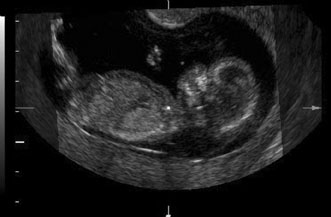

FIRST TRIMESTER ULTRASOUND

First trimester ultrasound may be performed transabdominally or transvaginally. Table 7 lists the components of a first trimester ultrasound. A crown–rump length, done between 7 and 13 weeks, can define a gestational age to within 5 days (Fig. 7).

Fig. 7. First trimester ultrasound showing crown–rump length.